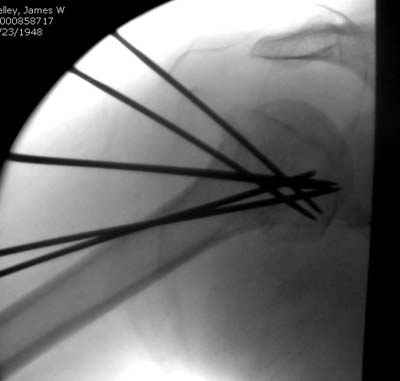

Сегодня взял больного повторно в операционную, не скажу, что повторная репозиция через неделю после первой попытки, была простая.

После удаления спиц попытался манипулировать отломками, но безуспешно, поэтому пришлось пользоваться периостальным элеватором, чтобы устранить смещение отломков и перепровести спицы. Проверил и перепроверил стабильность фиксации под ЭОПом, завтра Рг- будет готов, вот и поглядим....

Именно эти моменты+ дешевизна спиц и делают эту методику доступной практически в любых условиях (актуально для африканского государственного госпиталя). Хотя сейчас, пройдя через *подводные камни* понял , что для быстроты и простоты самой хирургии необходимо пользоваться drill sleeve and

wire guide, позволяющим ротировать пучок при его введении в головку (как объяснил Анатолий Ф.) Чтобы не терять время на поиск входного отверстия под мышцей удобно пользоваться drill sleeve 6,5 мм, удерживая его на кости после сверления отверстия, через него же провести и спицевой пучок, единственный момент который надо учитывать - чтобы размер петли не превышал диаметра протектора иначе придется начинать все сначала или в качестве альтернативы пользоваться разъёмными протекторами.